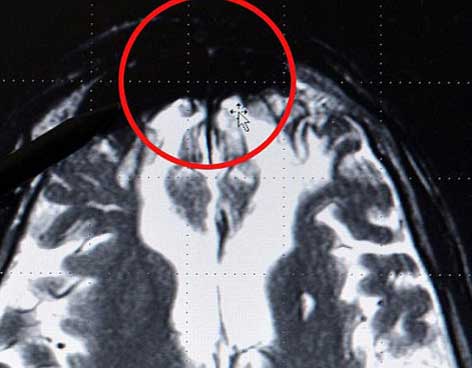

Sin embargo, en los escaneos cerebrales de las mismas personas, se veía una mancha oscura en la parte frontal, lo que supone que algunos criminales tienen una “predisposición genética” a la violencia.